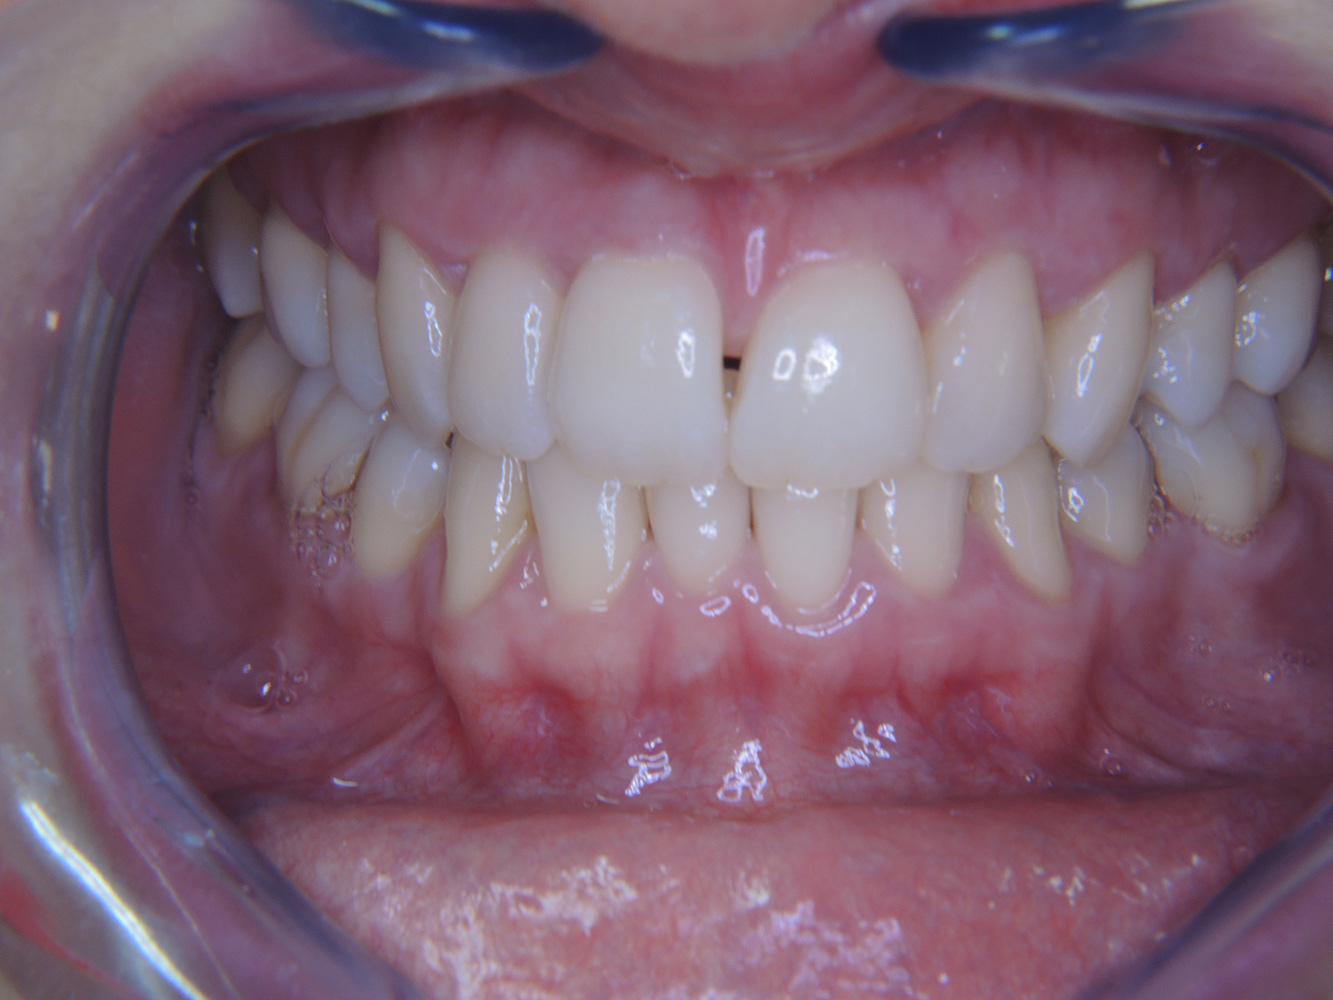

O pacientă diabetică de 51 de ani, cu o bună sănătate orală, se prezintă pentru o ședință de profilaxie. Glicemia este stabilă la HbA1c = 6.2%, prin urmare, se consideră că starea ei este suficient de bine gestionată cu medicamentul antidiabetic metformin. Pacienta nu prezintă lucrări dentare sau patologie orală. Cu ajutorul rezultatelor dentare, este posibilă determinarea gingivitei în ciuda condițiilor de altfel stabile. mai multe

The (orally) healthy patient with implants

In the medical history, the 55-year-old patient states that he has no systemic disease and is not taking any medication. The patient’s lifestyle is similarly unremarkable. The patient has a few tooth restorations and two implants (2nd and 4th quadrants). On the basis of current findings, gingivitis is identified in an otherwise stable periodontal condition on the reduced periodontium (stage III, grade A). more

The healthy patient with pre-existing periodontal disease & peri-implantitis

Pacientul diabetic cu boală parodontală preexistentă

This case report of a 52-year-old male with type 2 diabetes and periodontitis emphasizes personalized preventive measures and periodontal health maintenance to manage the moderate disease progression risk. mai multe...

Fumător de 28 de ani cu eroziuni dentare

28-year-old patient, smoker, with erosions. The bidirectional relationship between oral and general medical health is very well known. It is no longer sufficient – and arguably even old-fashioned – to consider intraoral conditions in isolation. In order to create a personalized, case-specific preventive and patient profile, it is essential to take a detailed medical history and perform diligent examination of the general medical and intraoral health, as well as considering the two in combination. more

Pacient cu endocardită cu leziuni carioase active

Pacientul are 39 de ani și a suferit anterior o înlocuire a valvei aortice din cauza unei insuficiențe de valvă și a unei endocardite. ASS 100 este administrat în mod regulat ca anticoagulant. În ceea ce privește stilul de viață, dieta pacientului este clasificată ca fiind favorizantă pentru carii, datorită consumului regulat de alimente zaharoase și a faptului că se consumă șase până la șapte mese pe zi. Sănătatea orală a pacientului indică un risc moderat de carii, cu leziuni active. Riscul de parodontoză este scăzut, dar gingivita este prezentă. Se fac următoarele recomandări pentru tratamentul profilactic. mai multe

Pacient transplantat cu proliferări gingivale

Un pacient în vârstă de 71 de ani, cu transplant de rinichi și istoric de hipertonie (hipertensiune arterială) se prezintă în cabinet. Din cauza istoricului său medical, este necesară o medicație pe termen lung cu ciclosporină, pentru a suprima sistemul imunitar, precum și amlodipină pentru a reduce tensiunea arterială. Pacientul raportează, de asemenea, gingii sensibile și sângerânde. Din punct de vedere al sănătății orale, pacientul are lucrări dentare, o edentație de opt dinți, creștere gingivală pronunțată și parodontoză de gradul B, stadiul II, cu pungi active și carii radiculare inițiale la dintele 22. Evaluarea riscului de carie determină un risc moderat de carie (API 60). Se pot stabili următoarele recomandări de tratament pentru ședința de profilaxie. mai multe

Pacient sănătos cu boală parodontală incipientă

Pacientul în vârstă de 68 de ani nu are nicio afecțiune generală și nu ia niciun medicament care ar putea fi relevant pentru sănătatea sa orală, iar stilul său de viață nu prezintă niciun risc special. Pacientul are două implanturi dentare (cadranul 3, de cinci ani) și un caz anterior de boală parodontală (stadiul IV, gradul B) cu pierderea dinților. În prezent, condițiile parodontale sunt stabile. Cu toate acestea, parodontoza crește semnificativ complicațiile biologice ale implanturilor și există riscul de pierdere a implanturilor (21). Se pot determina patru recomandări pentru ședința de profilaxie. mai multe